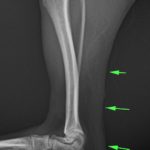

アキレス腱断裂 主治医よりアキレス腱断裂した患者さんが脚を着けなくなったので、なんとかして欲しいと連絡がありました。経関節ピンによる一時的な足根関節の仮固定とアキレス腱の縫合術により対応しました。しばらくは安静が必要です。 症例カテゴリー 放射線治療整形外科軟部組織外科脳神経外科内科腫瘍外科救急・集中治療リハビリテーション科腫瘍内科内視鏡科脳神経科呼吸器外科中医・漢方猫の腎移植循環器科